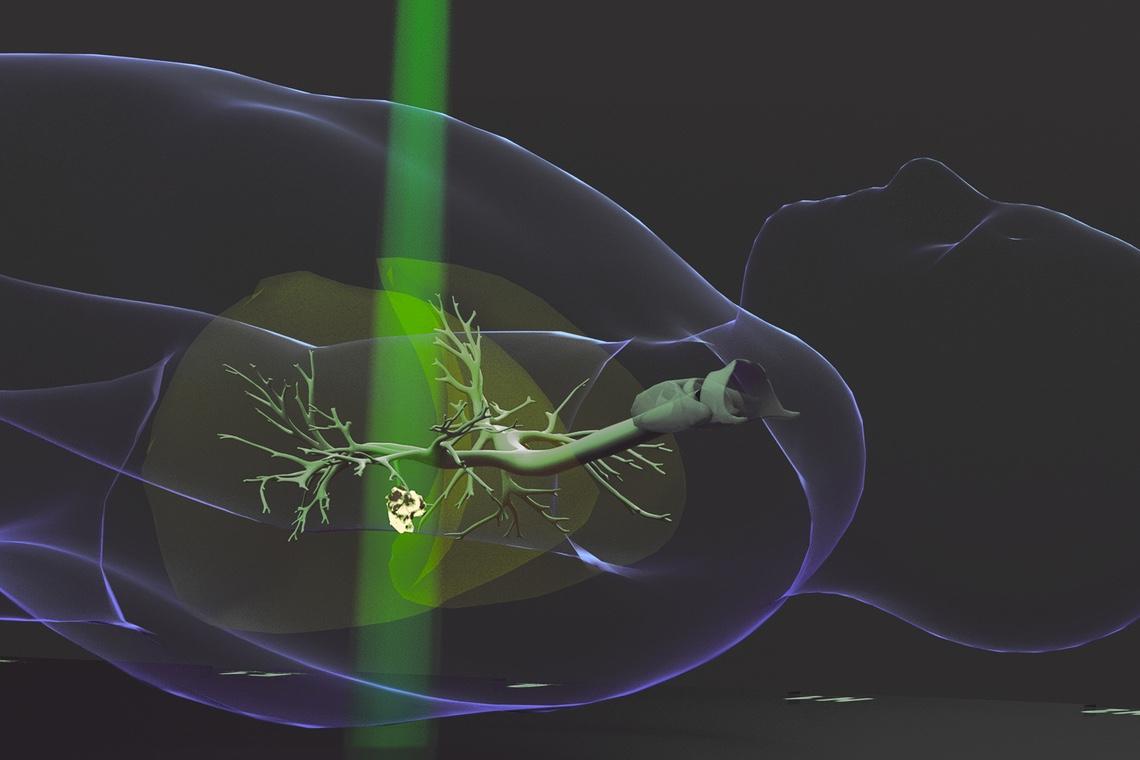

Pour tester leur nouveau cœur artificiel, son équipe s'est intéressée à une maladie appelée "régurgitation mitrale", qui touche environ 24,2 millions de personnes dans le monde. Dans ce cas, la valve mitrale située entre l'oreillette et le ventricule gauches du cœur ne se ferme pas correctement, ce qui signifie que le sang peut circuler dans le mauvais sens.

Les scientifiques ont utilisé un cœur de porc comme base, en retirant le muscle épais qui entoure le ventricule gauche et en le remplaçant par une pompe robotisée en silicone. Lorsqu'elle est gonflée, la pompe comprime et tord le cœur comme le ferait un vrai muscle.

En endommageant la valvule mitrale pour la rendre non étanche, l'équipe a pu permettre aux chirurgiens cardiaques d'intervenir sur le cœur biorobotique, en essayant trois techniques chirurgicales différentes pour corriger le problème : ancrer les tissus de la valvule pour qu'ils ne fuient pas ; implanter un dispositif pour aider la valvule à se fermer correctement ; remplacer complètement la valvule par une prothèse.

"Notre cœur artificiel peut servir de plateforme de formation chirurgicale pour les cliniciens et les étudiants en médecine. Il peut aussi permettre aux ingénieurs d'étudier leurs nouvelles conceptions et même aider les patients à mieux comprendre leur propre maladie et leurs traitements", concluent les scientifiques.